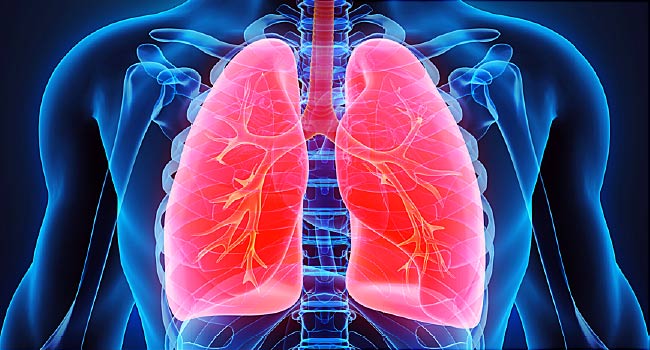

폐 (Lung)

위치와 구조

폐는 심장과 주요 혈관을 가운데 두고 좌우에 1개씩 2개가 있다.

오른쪽 폐는 크게 나눠 세개의 폐엽(우상엽, 우중엽, 우하엽)으로 나눌 수 있고

왼쪽 폐는 두개의 폐엽(좌상엽, 좌하엽)으로 나눌 수 있다.

오른쪽 폐가 왼쪽 폐보다 폭이 조금 더 넓지만 길이는 짧고 더 무거우며

전체 폐기능의 55%를 담당하고 있다.

일반 성인의 폐 무게는 약 400g 정도된다.